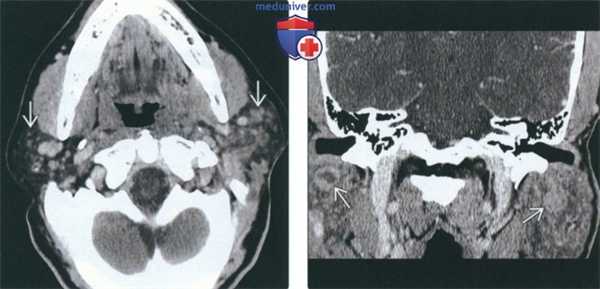

(Слева) На аксиальной КТ с КУ визуализируются множественные мелкие контрастирующиеся очаги с диффузным поражением обеих околоушных желез, характерные для персистирующей генерализованной паротидной лимфаденопатии. Данные очаги представляют собой увеличенные лимфоузлы.

(Справа) На корональной реформатированной КТ с КУ у пациента с ВИЧ определяются очаги в обеих околоушных железах, образованные кистозным и солидным компонентами, сопоставимые с ДЛЭП при ВИЧ.